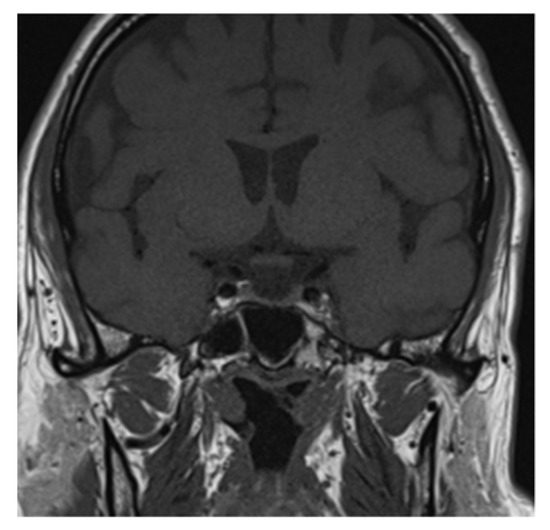

Clinical and laboratory findings were overall highly suggestive for immunotherapy-related adrenal insufficiency. Thereby, also pembrolizumab has been withheld and a low-dose steroid (dexamethasone 8 mg daily) was started, since the AE was classifiable as G2. Liquid restriction to a maximum of one liter per day was prescribed in order to control electrolyte impairment. After three days, the symptoms already improved. Further investigation with brain magnetic resonance imaging (MRI) was performed and it revealed a pituitary gland reduced in size, thin, and lying along the floor of the sphenoid sellae, consistent with partial “empty sellae syndrome” (Figure 1 and Figure 2). This finding led to a definitive diagnosis of iatrogenic hypophysitis and so secondary adrenal insufficiency. An endocrinological examination was performed and specific hormonal replacement therapy (HRT) with cortone acetate 37.5 mg daily was prescribed.

Figure 2. Partial “empty sellae syndrome” on brain MRI coronal section.